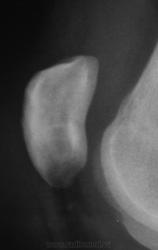

Такую фрагментацию видели и не раз. Вопрос в другом и в основном к детским рентгенологам-бывают ли такие варианты развития надколенника с неполным консолидированием ядер?

А, может "бипарцита"?

Один из вариантов patella bipartita

Процесс бессимтомный и практически всегда двусторонний - второй сустав в прямой проекции.

Bipartita